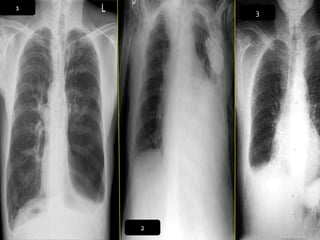

1

3

2

CRITERIOS DE EVALUACIONRX. TX.  Pulmones desde ápex hasta senos costo diafragmáticos  Pulmones y corazón sin rotación.  10 pares de costillas.  Sombra área de la tráquea centrada sobre la columna.  Balance en los contrastes de la imagen (exposición adecuada).

INTERPRETACION  Revisar estructuras óseas.  Partes blandas.  Espacios intercostales.  Parénquima pulmonar  Nivel de los senos costodiafragmaticos.  Neumatización.  Trama alveolo-pulmonar  Silueta cardiaca  Cayado aórtico.

1 3 2